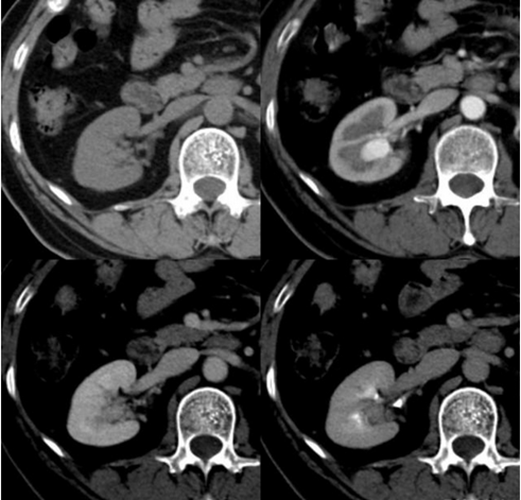

糖尿病腎病變圖片